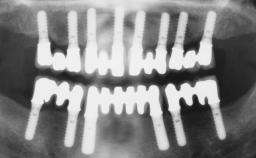

Immediate Loading of Six Implants in the Maxilla and Final Restoration with a Full-Arch Gold/Ceramic FDP Involving the Concept of Tilted Implants

A 61-year-old male patient with a failing fixed maxillary rehabilitation and a fixed mandibular rehabilitation requested a new fixed maxillary rehabilitation. The patient was wearing a temporary metal-reinforced maxillary bridge inserted two years before the consultation. He reported that his previous dentist did not want to insert a definitive framework because he considered the residual teeth to have a negative prognosis. The patient reported a history of recurrent caries and endodontic complications as the main reason for the previous extractions. The anamnesis was negative for periodontal disease and bruxism. The patient’s chief compliant was the mobility of his maxillary prosthesis, which needed to be re-cemented frequently, and discomfort during chewing.Moreover, the patient was not satisfied with the esthetic appearance of his maxillary teeth, which he found too long. The patient asked for a stable and comfortable fixed maxillary rehabilitation and firmly rejected any removable solution.

# of Implants 6

Bone Augmentation Horizontal|Simultaneous